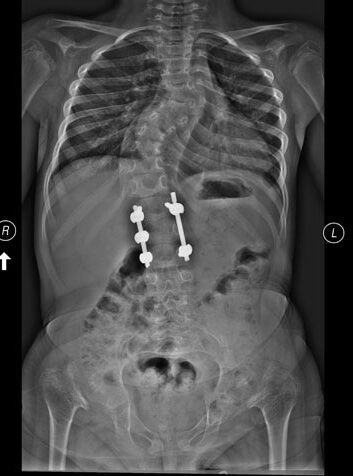

Od samego początku zdawaliśmy sobie sprawę, że w przyszłości Kasię będzie czekać operacja kręgosłupa. Córka urodziła się z dodatkowym półkręgiem w części piersiowej, który powoduje postępującą skoliozę i niebezpiecznie zbliża się do rdzenia kręgowego. Oznacza to, że bez operacji nastąpi paraliż jej ciała. Kasia przestanie poruszać rękami i nogami, utraci to, na co tak ciężko i długo pracowała! Nawet nie chcę o tym myśleć, odsuwam ten koszmar, lecz on wciąż mnie nawiedza. Dr Feldman, który opiekuje się Kasią nie może zoperować kręgosłupa w Paley European Institute w Polsce, nie ma tu odpowiedniego zaplecza do tak skomplikowanej interwencji chirurgicznej, natomiast polscy specjaliści oferowali drogę leczenia, która nie budziła mojego zaufania, a po tym co przeszła moja córka nie mogę absolutnie ryzykować! Dr Feldman nie chce przesuwać operacji w czasie, skolioza postępuje szybko, za chwilę może być za późno. Operacja ma się odbyć latem 2024 r. Kwota do zebrania jest tak wielka, że nawet boję się ją napisać… To 150 000 USD, czyli ok. 646 000 zł! Kasia przeszła już 11 operacji, po zabezpieczeniu kręgosłupa, będzie mogła w końcu odetchnąć, nie myśleć o kolejnym bólu, szpitalu, unieruchomieniu, izolacji… Zacząć cieszyć się dzieciństwem, na jakie zasługuje!

2. Operacja kręgosłupa oraz 2 operacje bioder w Schön Klinik Vogtareuth (2017–2019).

Pod koniec kwietnia 2017 r. Kasia przeszła w klinice specjalistyczne badania kręgosłupa, które miały dać lekarzom pełny obraz dalszego przebiegu jej leczenia. Po konsylium lekarze zdecydowali, że operacja jest zbyt niebezpieczna. Mogła uszkodzić rdzeń, dlatego trzeba było ją podzielić ją dwa etapy. W styczniu 2018 r. odbył się pierwszy z nich – ustabilizowanie odcinka lędźwiowego. Równo rok później (30.01.2019) Kasia pojechała do Niemiec na operację lewego biodra. Wszystko poszło zgodnie z planem i dwa miesiące później (19.03.2019) lekarze mogli zoperować prawe biodro. To była 7 tak poważna operacja w życiu dziewczynki. Dzięki nim wszystkim oraz intensywnej, codziennej rehabilitacji zaczęła samodzielnie chodzić w ortezach, jeździć na rowerze, wchodzić po schodach, uczęszczać do przedszkola…